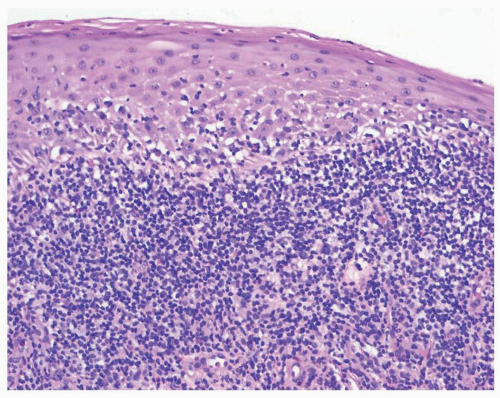

Histologic features of erosive lichen planus include a dense, lymphocytic, dermal bandlike infiltrate extending to and damaging the basal layer (Fig. 11.14). A prominent granular cell layer, hyperkeratosis, and acanthosis are common, but erosive mucous membrane lichen planus often exhibits epithelial thinning and flattening. A biopsy of eroded skin that does not include epithelium cannot demonstrate a diagnosis of lichen planus, so biopsy sampling should include the epithelialized edge of an erosion. Colloid and Civatte bodies are frequently seen in the lower epidermis and upper dermis, and a direct immunofluorescent biopsy makes these more easily visualized.

![]() FIG. 11.14. A biopsy of mucosal lichen planus usually shows a lichenoid infiltrate of chronic inflammatory cells in the upper dermis abutting and destroying the basal cell layer. |